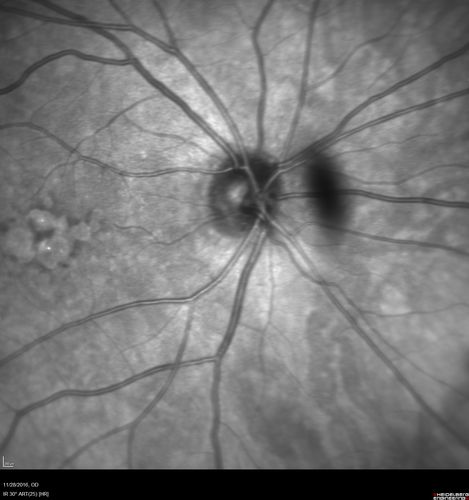

Confluent Soft Drusen with Subetinal Fluid - Right Eye

Asymptomatic 85 year old man.  OCT shows pocket of subfoveal fluid in the center of the macula.  This could be mechanical from the drusen preventing the retina from settling down.  Testing did not reveal a CNVM and subsequent OCT 6 weeks later showed no change in structure.